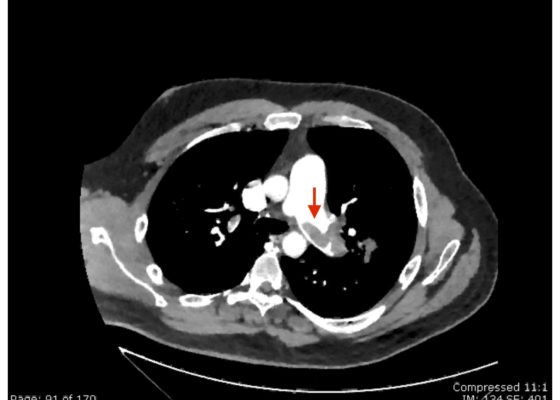

DOI: https://doi.org/10.21980/J8N63PAn electrocardiogram (ECG) showed evidence of right heart strain with an incomplete right bundle branch block, S1Q3T3 (see red arrow [S1], blue arrow [Q3], and black arrow [T3]), and ST-segment elevation in the septal leads (green arrows). Bedside echocardiography showed a dilated right ventricle with ventricular wall akinesis (red arrow) sparing the apex (purple arrow), which is known as McConnell’s Sign. It also showed a mobile hyperechoic mass (yellow arrow). These ultrasound findings were concerning for pulmonary embolism (PE), so computed tomography (CT) angiogram of the chest was ordered and confirmed massive bilateral obstructive filling defects (red arrows) consistent with saddle pulmonary embolism. Additionally, noted is flattening of the interventricular septum (blue arrow) consistent with right heart strain. Laboratory studies were notable for a troponin-I of 0.29 ng/mL, a B-type natriuretic peptide of 792.3 pg/mL, lactic acid of 5.30 mmol/L, and a creatinine of 2.0 mg/dL, consistent with end organ dysfunction. All other lab work was within normal limits.